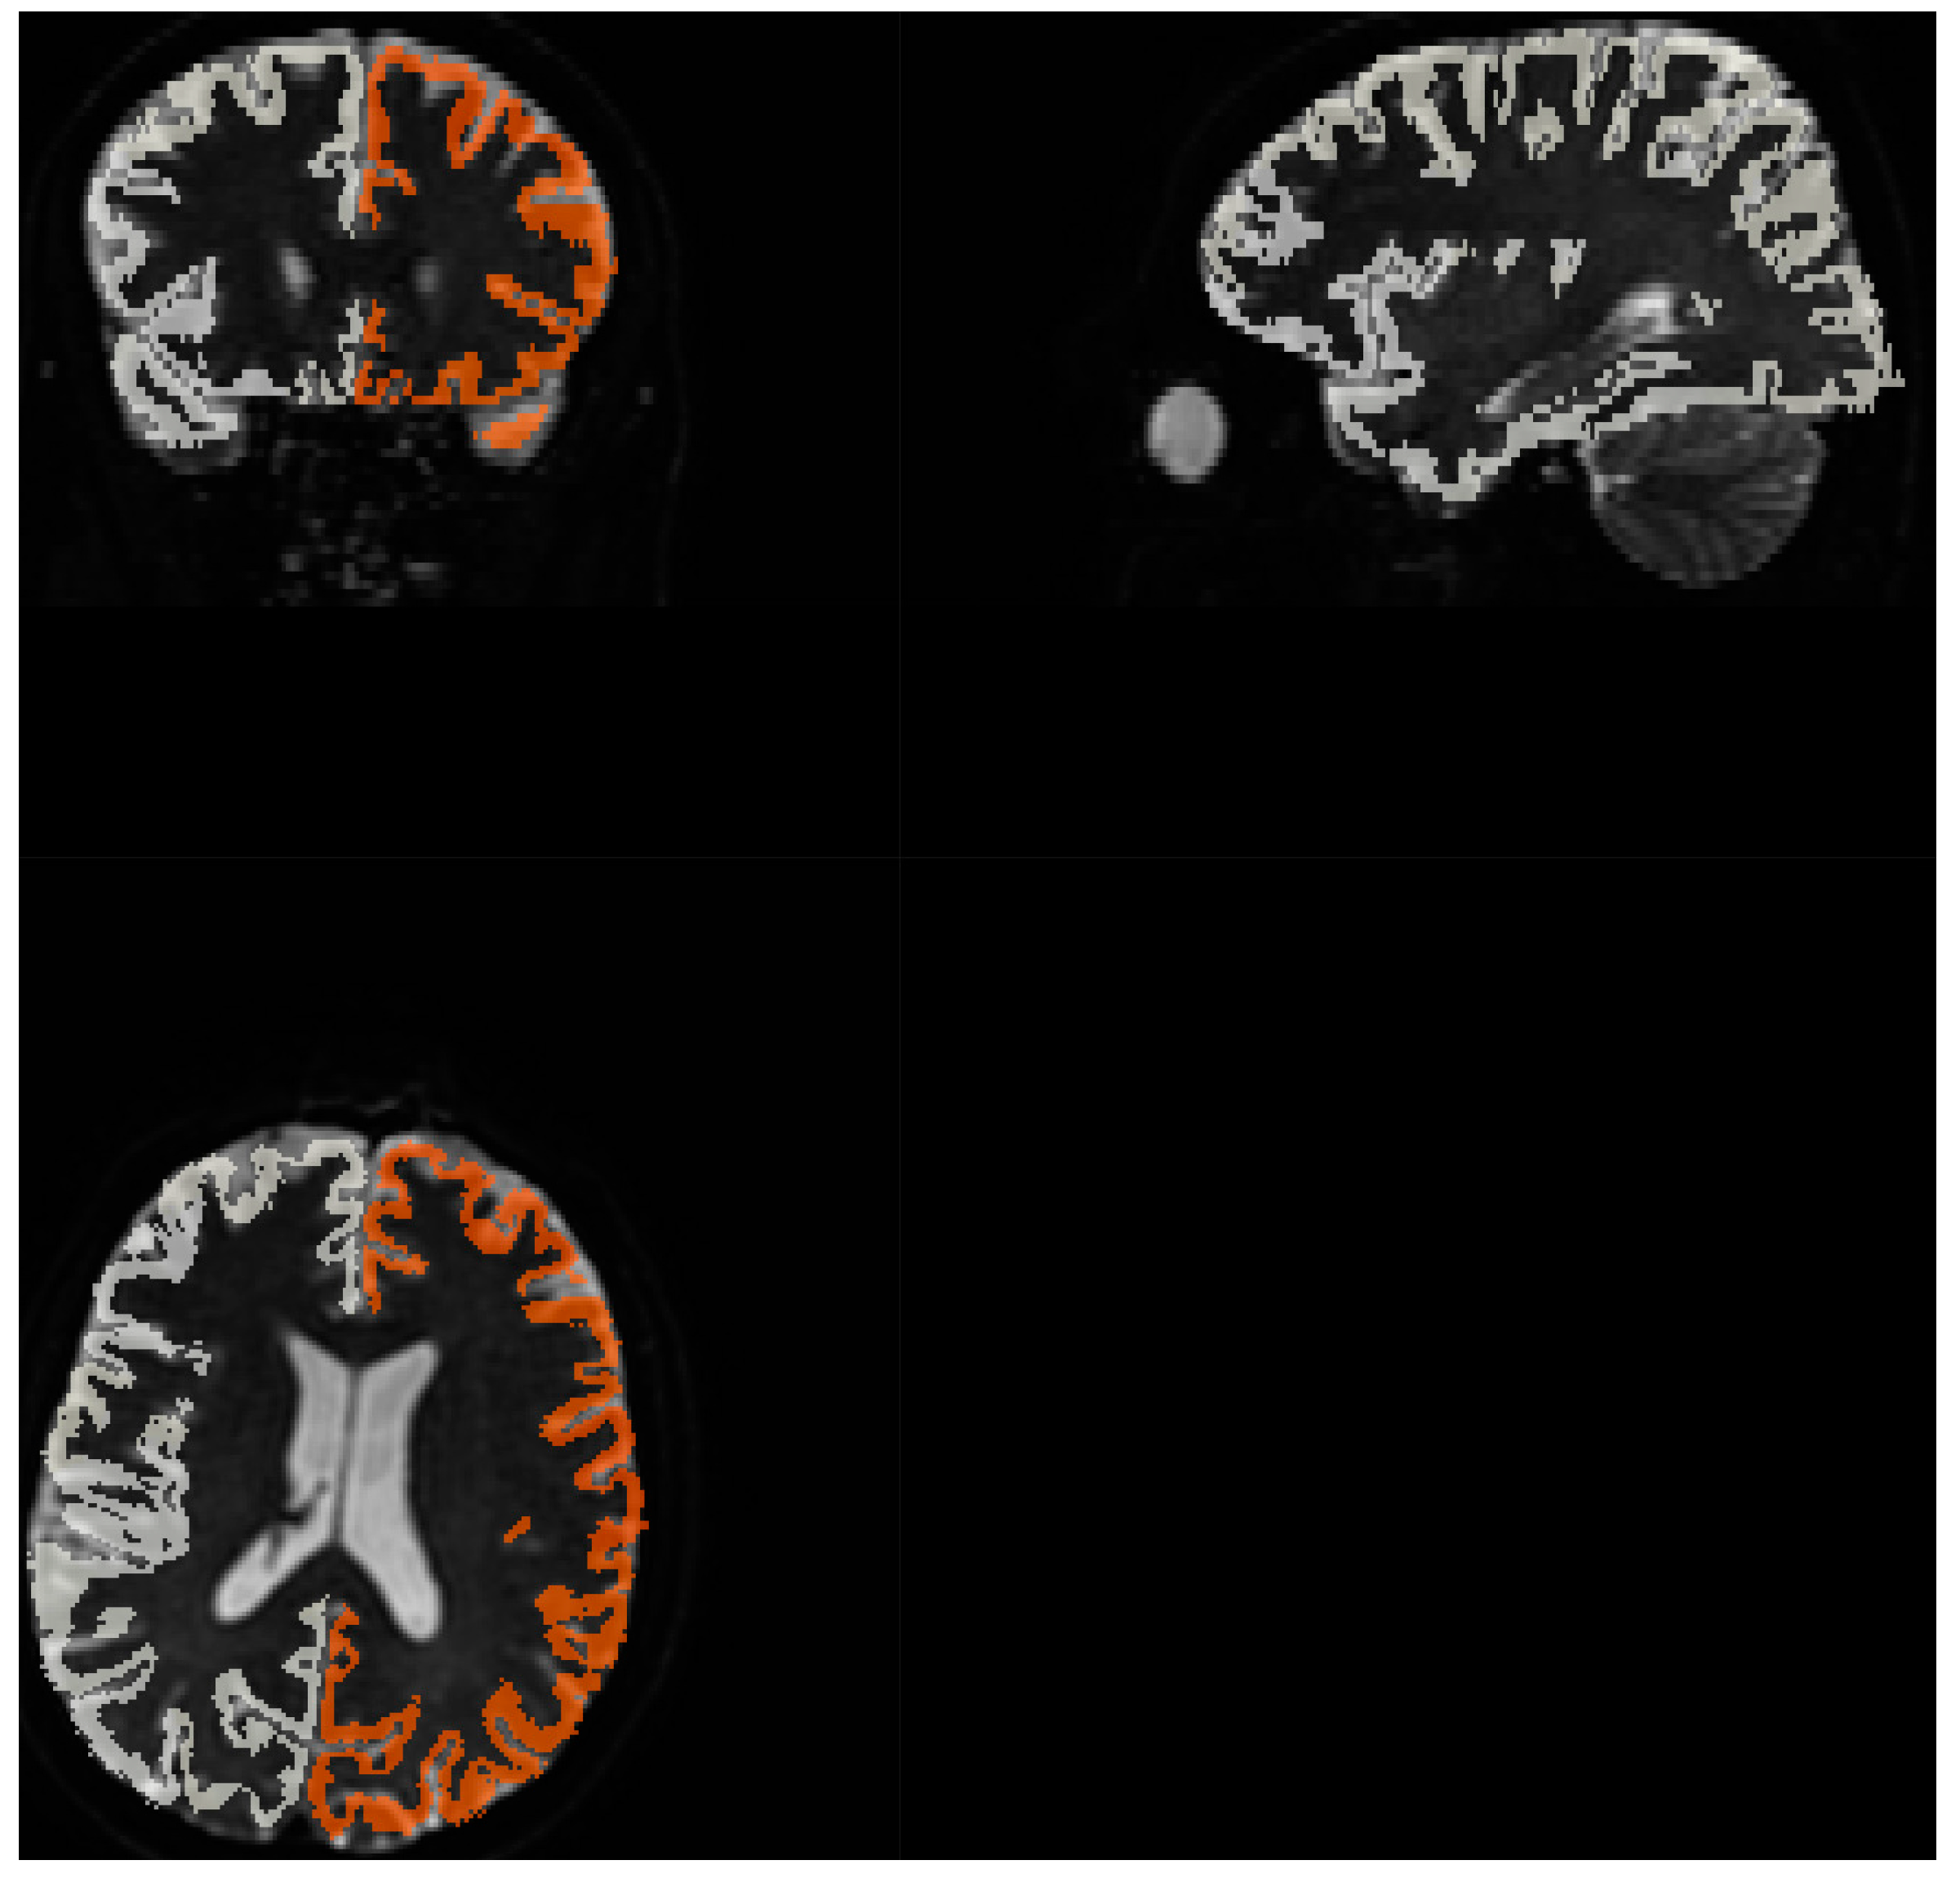

Figure 8. Brodmann areas atlas overlayed on DWI scans. Orange and gray shape represent the coverage of Brodmann atlas template, regridded to IVIM DWI resolution.

The diffusion data went through a preprocessing procedure, involving five steps: denoising, removal of Gibbs ringing artifacts, correction of susceptibility-induced distortions, eddy current correction, and DWI bias field correction. Denoising was performed using Marchenko-Pastur Principal Component Analysis [16,17,18],while Gibbs ringing artifacts was mitigated through the method of local subvoxel-shifts [19], and implemented in MRTrix [20]; susceptibility induced distortions correction and eddy current correction was corrected using FSL [21]; and B1 Inhomogeneity correction using N4 algorithm [22] implemented in ANTs [23]. Preprocessed data underwent brain extraction procedure with MRTrix. SNR was calculated from 5 b 0 scans as mean signal and standard deviation quotient in MATLAB [24] for brain extracted images. Normalization of IVIM data to MNI152 space [25] using MRTrix algorithms. To match structures in MNI space, patient’s b 0 scan underwent extraction that was followed by brain masking. Subsequently, the histogram of the extracted image was non-linearly adjusted to match the histogram of symmetrical 1mm3 T2 template. The image was then registered to the template using affine, followed by non-linear transformation. Two transformation matrices were computed: one for aligning the patient’s image to the template space and another for aligning the template to the patient’s space. Using abovementioned transform, Brodmann atlas aligned in MNI space [26] was transformed to patient space and regridded to IVIM data using nearest neighbor interpolation method. Quality of matching was visually inspected. IVIM parameter estimations for 80 Brodmann areas (40 from left and 40 from right hemisphere) were computed based on the averaged signal from the specified region after normalizing each voxel to its maximal value.

FSL FMRIB’s Automated Segmentation Tool was used on T1 and T2 image to create white matter and gray matter maps. As T1 and IVIM MRI were acquired as first and last imaging sequence respectively, thus coregistration of T1 to b 0 IVIM scan was necessary because of discrepancies in spatial alignment caused by patient movement. This coregistration was performed using SPM12 [27] using Normalized Mutual Information objective function. Similarly to the above IVIM parameter estimations for white matter and grey matter were computed based on the averaged signal from the region after normalizing each voxel to its maximal value.

Fitting to template performed using MRTRix. Results are depicted on Figure 8

Acquiring high resolution IVIM DWI allowed for precise spatial alignment with template/atlas, as evidenced on Figure 8. Visual observation leads to conclusion that Brodmann areas atlas is mostly well aligned with cortical structures.